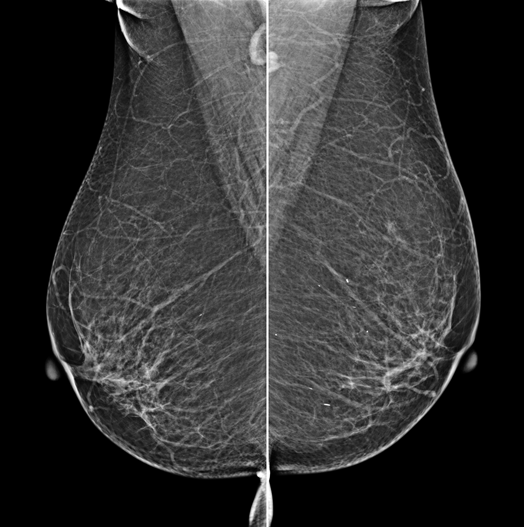

The X-ray tube moves on the breast and takes high-definition, high-resolution images with high contrast from various angles.

The images are reconstructed in 3D to provide accurate information about the location and condition of the lesion.

HESTIA supports "Synthetic 2D" that generates 2D images only by tomography shooting without additional 2D shooting.

GENORAY's know-how that was accumulated for a long time gives the best diagnostic images.